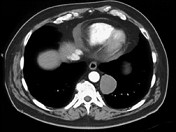

- 单项选择题男,33岁, 背部不适,无发热, 结合CT图像,选择最可能的诊断是 ( )

A、椎旁脓肿

B、神经源性肿瘤

C、脑脊膜膨出

D、食管囊肿

E、淋巴瘤